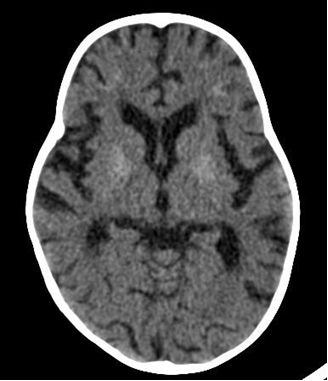

Diagnosis: Diagnosis is clinical, however, where available, neuro-imaging of the brain may show basal ganglia calcification, cerebral atrophy, and white matter changes.